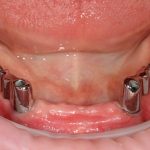

Рекомендации по установке имплантов. Для всех. Часть III